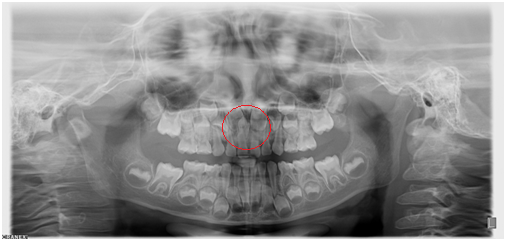

【全景牙片】

◆乳牙的萌出和替换

◆多生牙

◆阻生智齿

◆牙周炎引起的牙槽骨吸收